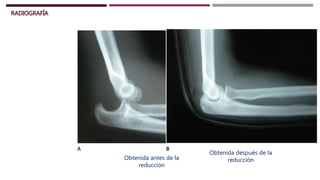

RADIOGRAFÍA

Obtenida antes de la

reducción

Obtenida después de la

RADIOGRAFÍA Obtenida antes dela reducción Obtenida después de la reducción